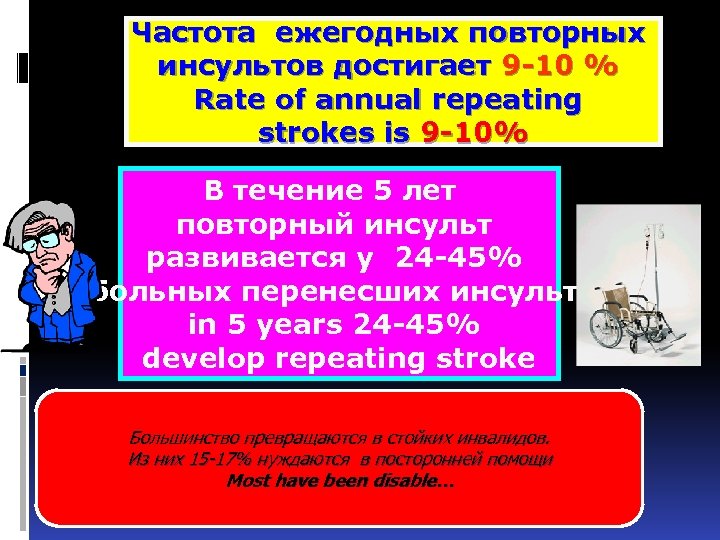

Частота ежегодных повторных инсультов достигает 9 -10 % Rate of annual repeating strokes is 9 -10% В течение 5 лет повторный инсульт развивается у 24 -45% больных перенесших инсульт in 5 years 24 -45% develop repeating stroke Большинство превращаются в стойких инвалидов. Из них 15 -17% нуждаются в посторонней помощи Most have been disable…

Частота ежегодных повторных инсультов достигает 9 -10 % Rate of annual repeating strokes is 9 -10% В течение 5 лет повторный инсульт развивается у 24 -45% больных перенесших инсульт in 5 years 24 -45% develop repeating stroke Большинство превращаются в стойких инвалидов. Из них 15 -17% нуждаются в посторонней помощи Most have been disable…